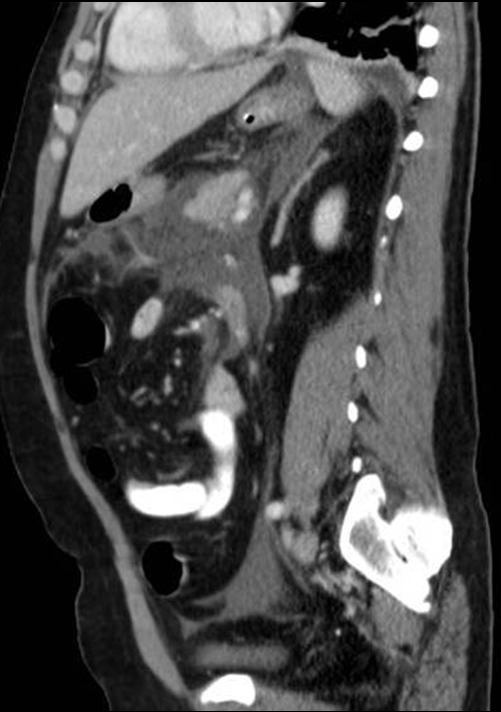

• A knife falling from a kitchen table stuck into the right thigh of an 18 year old young man. Increased femoral circumference and pulsating mass were seen. In the upper image with femoral Duplex sonography pseudoaneurysm of the femoral artery is detected

In the middle with a CT angiography the pseudoaneurysm shows contrast enhancement.

In the lower image 3D reconstruction of the CTA

11. A knife falling from a kitchen table stuck into the right thigh of an 18 year old young man. Increased femoral circumference and pulsating mass are seen. In the upper image with femoral Duplex sonography pseudoaneurysm of the femoral artery is detected In the middle with a CT angiography the pseudoaneurysm shows contrast enhancement. In the lower image 3D reconstruction of the CTA